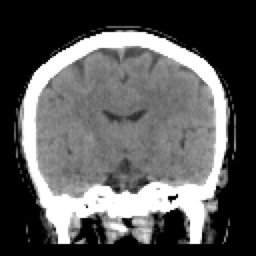

SIMPLE FINO COR (8) 91 images

ARTERIAL FINO COR (10) 90 images